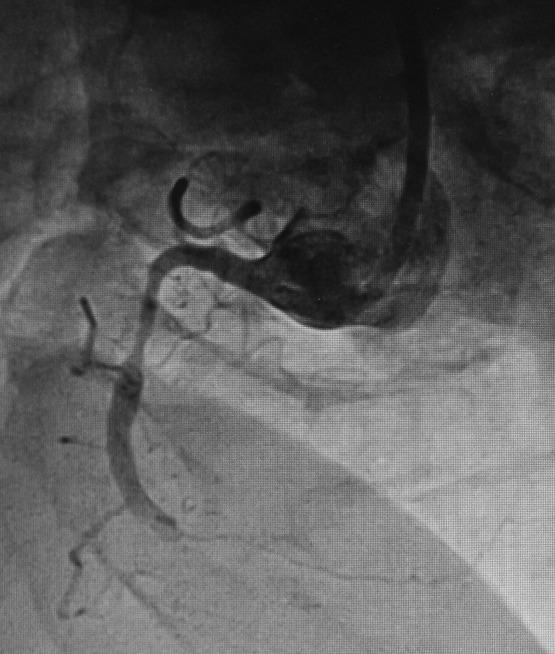

Development of coronary artery aneurysm (CAA) after implantation of drug-eluting stent is occasionally observed. We present a case of a 67-year-old man who underwent everolimus-eluting stent (EES) implantation in right coronary artery (RCA) for inferior wall myocardial infarction, and thereafter, giant CAAs were developed in the vessel of stent deployment, within 2 months. However, the patient was managed with coronary artery bypass grafting (CABG). On follow-up, the patient's condition was stable. To the best of our knowledge, we report the first case of occurrence of EES-associated giant CAAs in RCA subsequently treated with CABG.

摘要

药物洗脱支架植入后偶尔会观察到冠状动脉瘤(CAA)的发生。我们报告一例67岁男性患者,其因下壁心肌梗死在右冠状动脉(RCA)植入依维莫司洗脱支架(EES),此后在支架置入血管内2个月内出现巨大CAA。然而,该患者接受了冠状动脉旁路移植术(CABG)治疗。随访时,患者病情稳定。据我们所知,我们报告了首例RCA中发生EES相关巨大CAA并随后接受CABG治疗的病例。